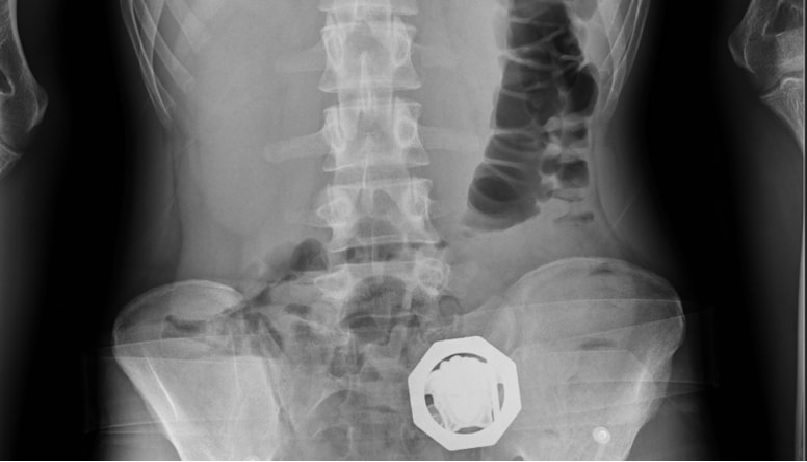

وتظهر الاشعة المقطعية للمتهمين داخل مصلحة الطب الشرعي وجود 33 حبة زنة 224 جران و40 حبة زنة 285 جرام و48 حبة زنة 840 داخل معدتهم.